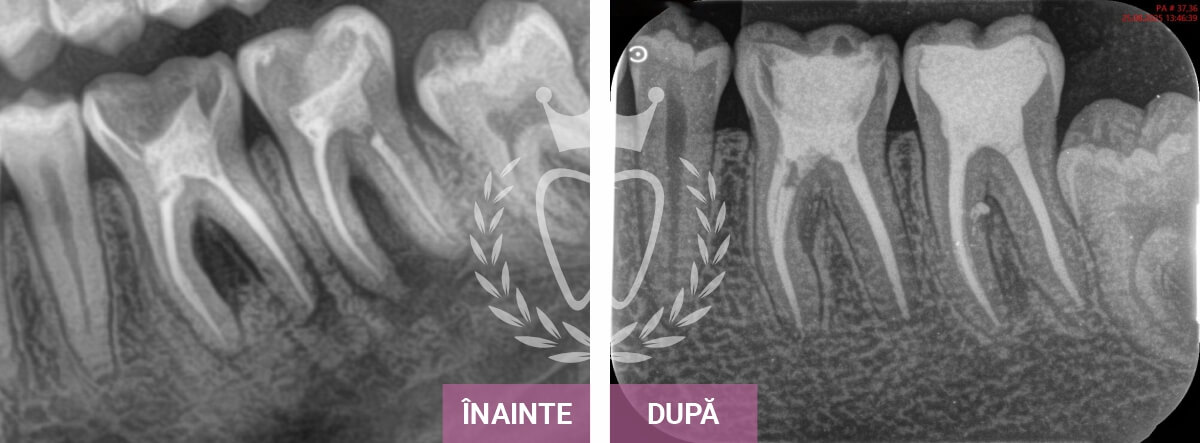

Îți prezentăm o selecție de cazuri care evidențiază rezultatele tratamentelor stomatologice realizate de echipa noastră.

De la implanturi dentare și tratamente ortodontice, până la endodonție, protetică și estetică dentară, fiecare caz reflectă grija, experiența și atenția oferită fiecărui pacient, pas cu pas.